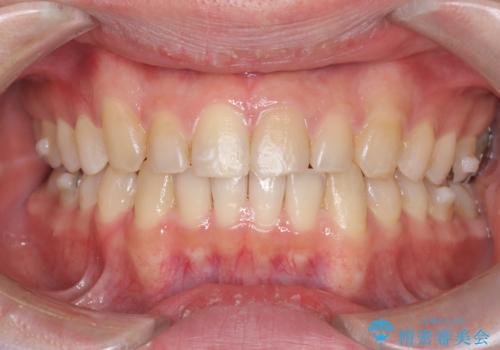

正中離開・クロスバイト・すきっ歯・叢生|インビザラインで治療

- 前歯の隙間と歯のデコボコを主訴にご来院された患者様です。

加えて、上下の奥歯が全く咬み合わないシザーズバイトの状態も認められました。

矯正検査の結果、非抜歯でインビザラインによる治療が可能と判断し、治療を行いました。

歯の隙間とデコボコ、シザーズバイトも改善され、咬み合わせや見た目が整い、患者様にも大変ご満足いただけました。